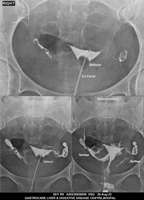

Section: HSG

Total: 49 Cases

All Categories BaM Enteroclysis Loopogram BaE Fistulogram Urethrogram HSG